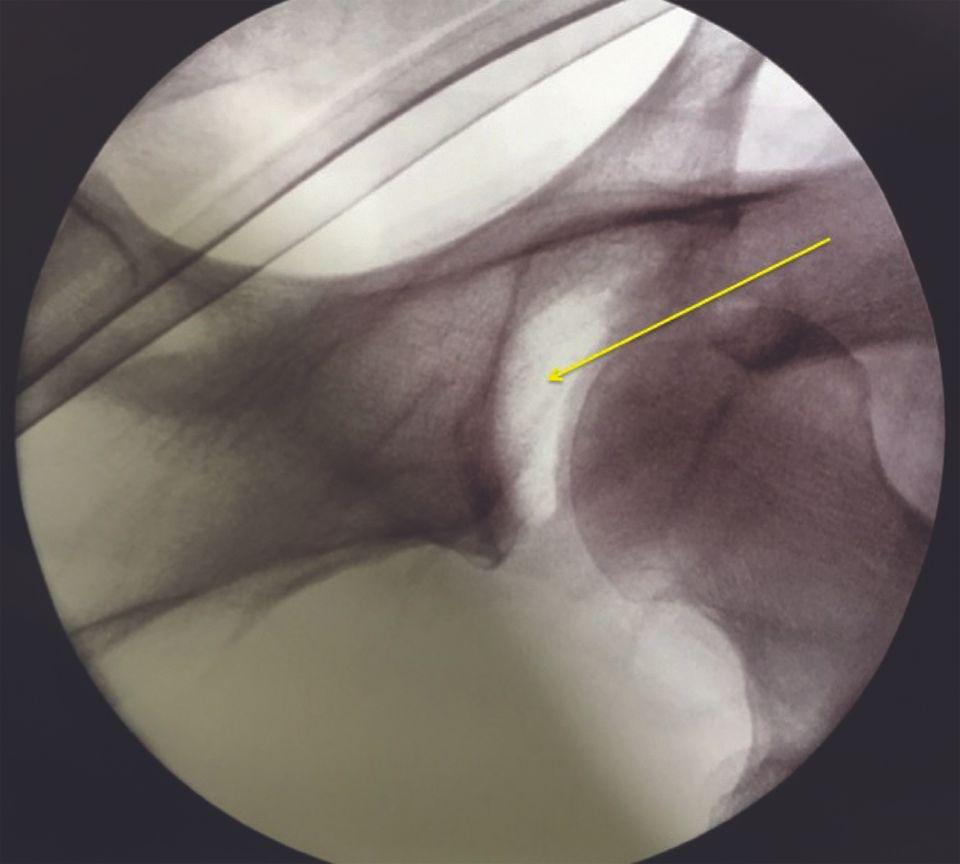

It makes it possible to view a sufficient space between the apex of the femoral head and the roof of the acetabulum to facilitate the insertion of the different trocars. The traction is deemed effective when a light-coloured crescent at least 10 mm thick appears in the coxofemoral joint (Fig. 2).

The entry point in the skin is made where the line passing over apex of the greater trochanter (perpendicular to the ASIS–patella line) intersects with the line mapping the anterior edge of the femur. This point is situated approximately 1 cm above and 1 cm in front of the greater trochanter (Fig. 3, left). Using the image intensifier, if the patella is facing up, the needle will be parallel to the floor and pointed towards the clear space in the separated joint (Fig. 3, right).